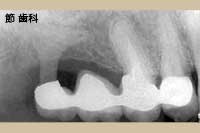

③ これも上の症例と同じものですが、インプラントの底部が上顎洞底線にタッチするように埋入処置が行われていることが確認できます。当時の“人工サファイヤ”タイプのインプラントは、「単独植立」を前提としておらず、隣在歯と連結するやり方が基本となっていました。